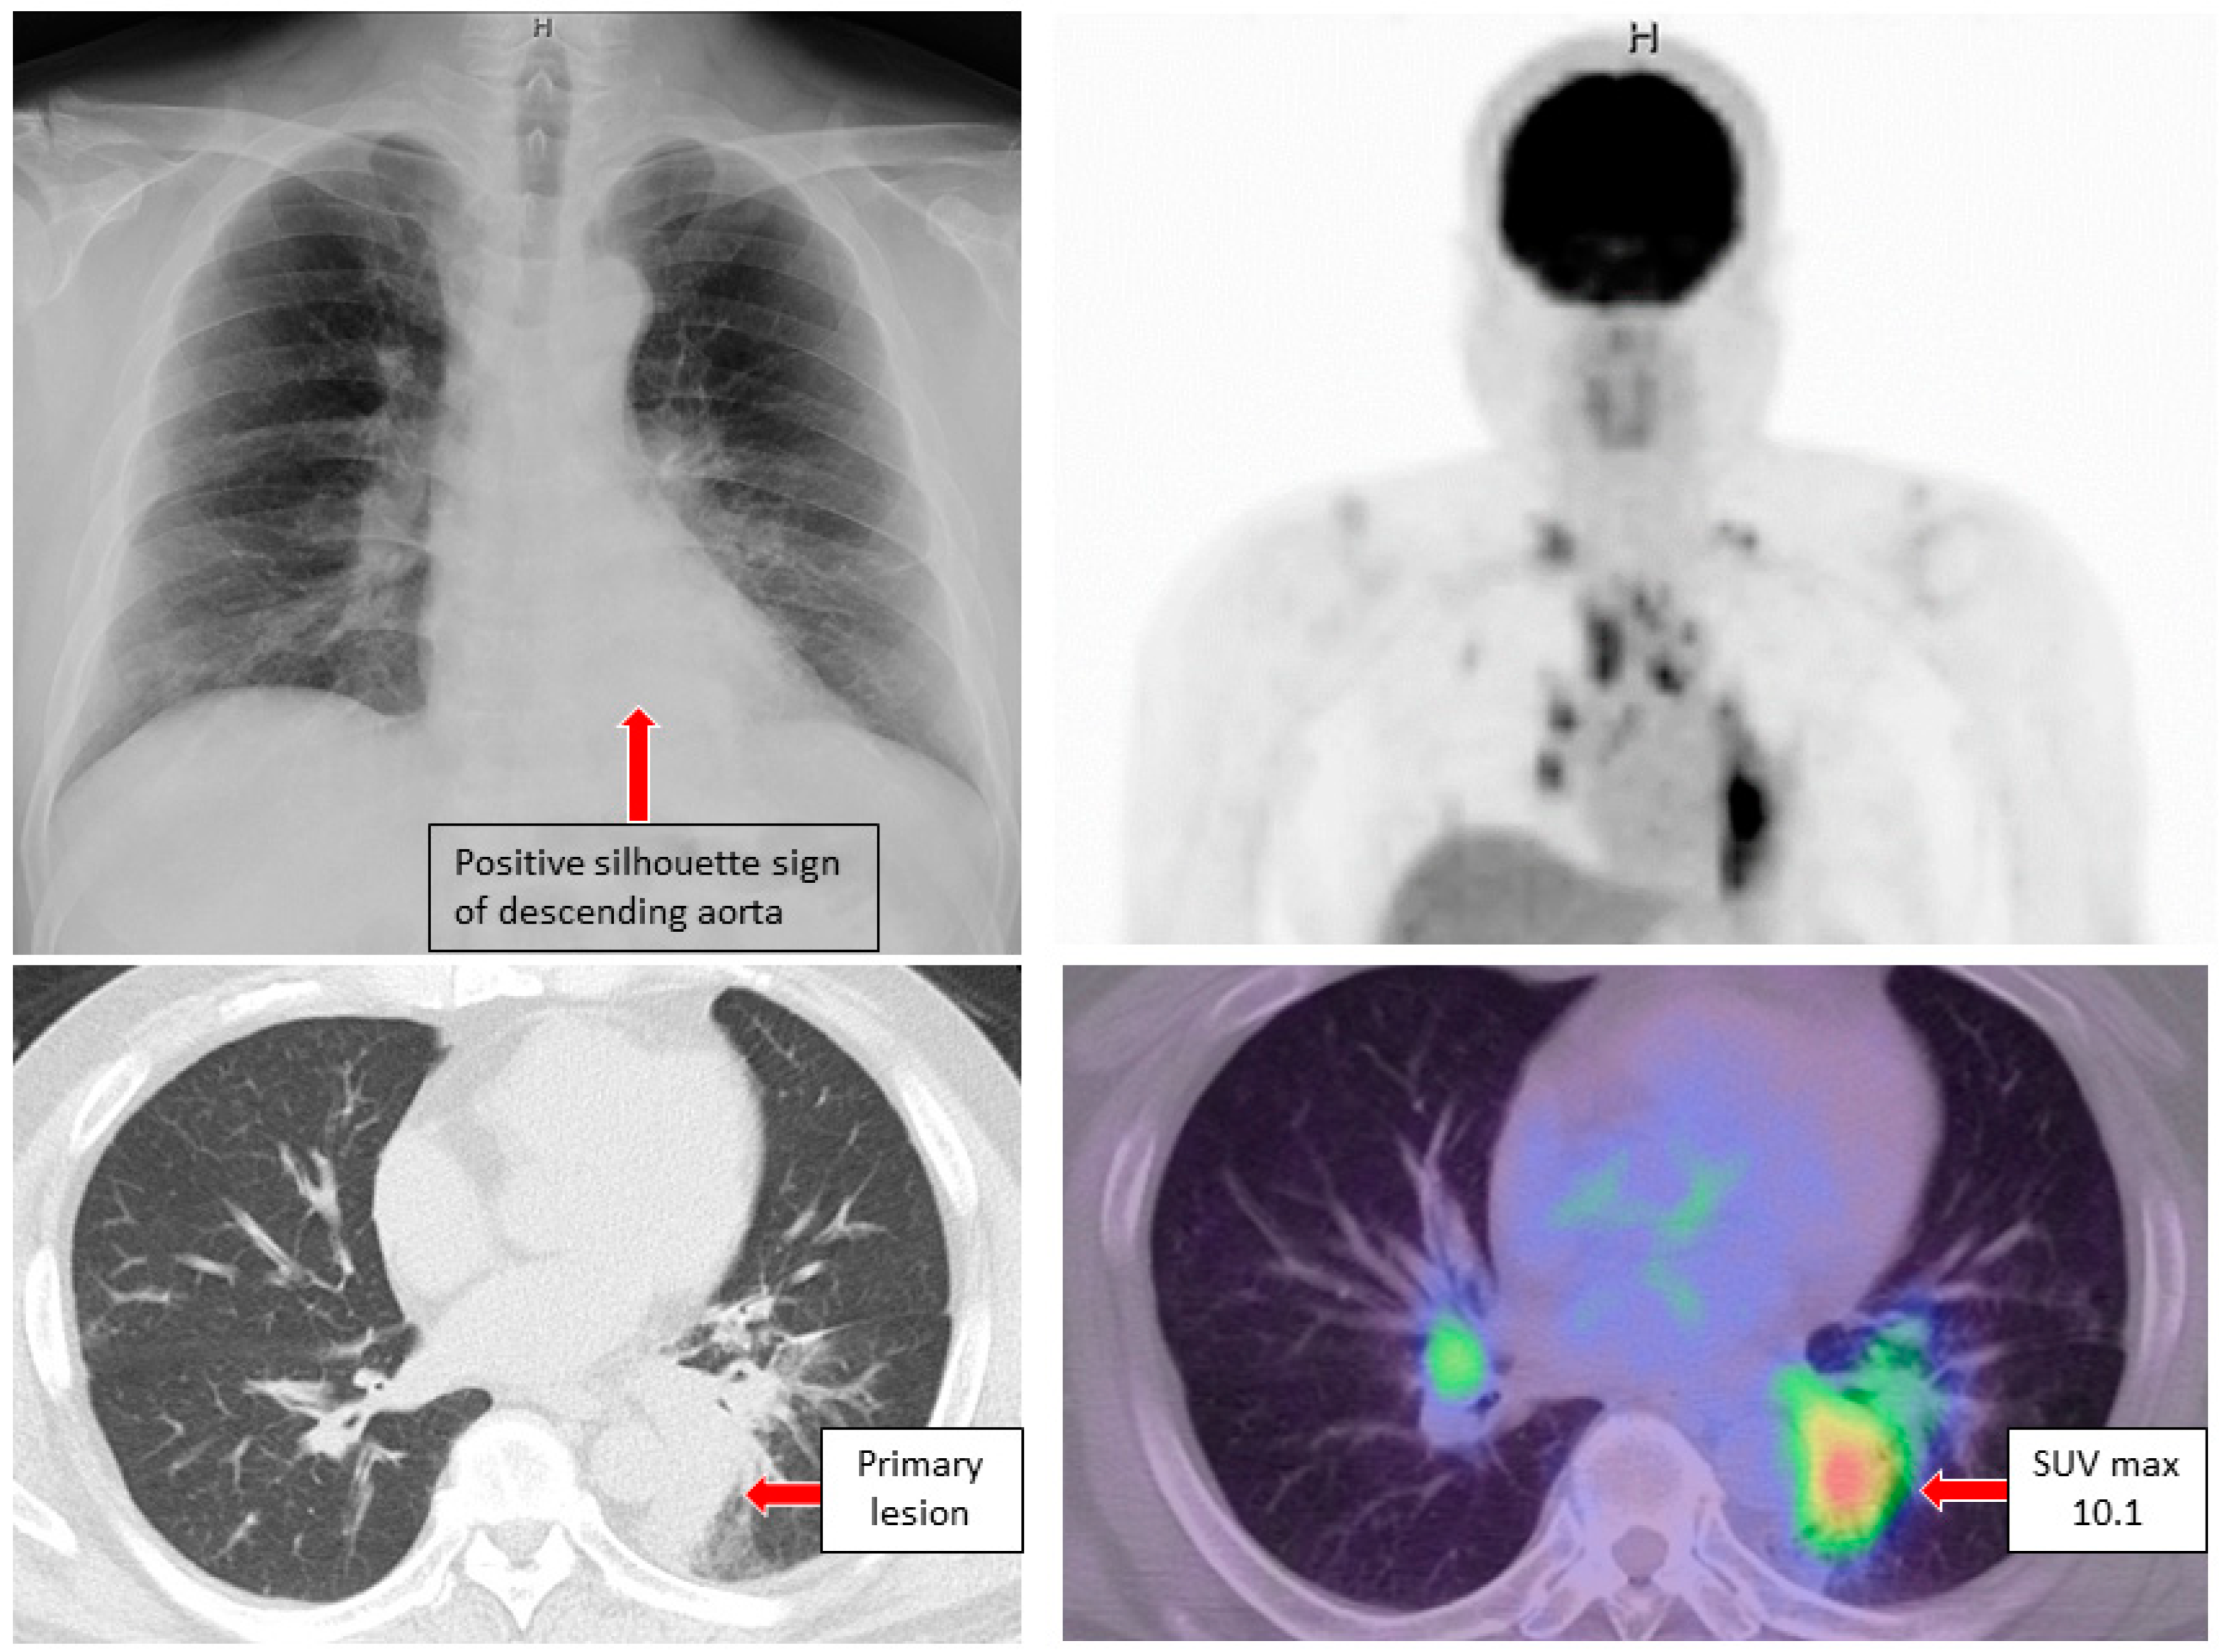

3. Case Reports